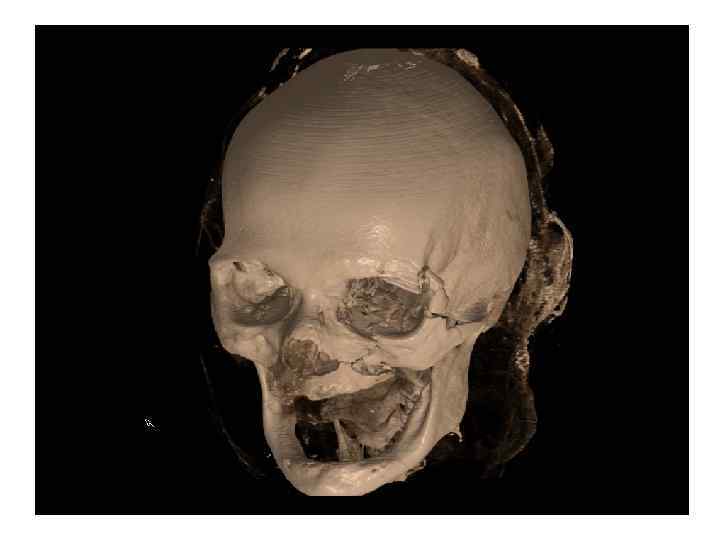

Перелом по типу Лефор II СКТ 3 D

Перелом по типу Лефор III Костный фрагмент представлен верхней челюстью со скуловыми костями. Верхнечелюстная пазуха, скуловой отросток и подглазничный край не повреждены. В медиальном отделе линия перелома проходит аналогично 2 типу, а в латеральных отделах по лобно-скуловому шву и скуловой дуге.

Перелом по типу Лефор III